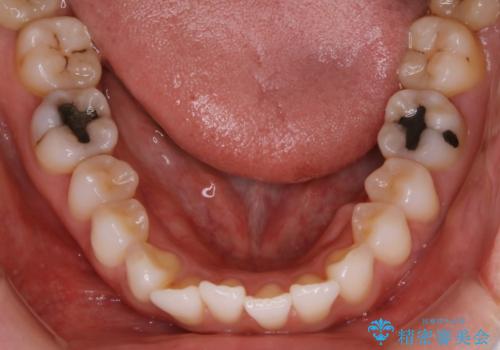

【非抜歯】前歯のガタつき マウスピースの部分矯正

- 上下の前歯の細かいガタつきの治療をご希望されて来院されました。

奥歯部分にはガタつきや噛み合わせの問題などがほとんど見られず、前歯のガタつきも軽度だったため、インビザライン ライト パッケージでの部分矯正を行うこととなりました。

今回のケースでは奥歯の噛み合わせに問題がほぼみられなかったため、前歯の位置のみに焦点を当て部分矯正を行いました。